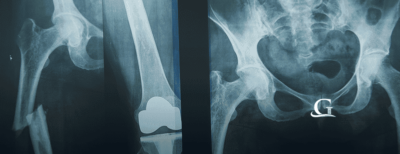

Hip replacement surgeries are one of the most common joint replacement procedures performed in the U.S. Metal-on-Metal hip implants have known to cause problems in patients that are debilitating. In some instances, the metal-on-metal causes a condition known as metallosis, which is caused from microscopic metal particles that is shed from the metal-on-metal joint replacement and is embedded in a person’s tissue. The result of exposure to these toxic materials is the subject to many lawsuits.

Many of the patients that have received the hip replacement surgery are scheduled to be operated on again for revisions. These procedures are costly and while somewhat effective still do not guarantee the patient will not have problems in the future. If you or a loved have had a faulty hip replacement, contact the Goldwater Law Firm today. We will continue to post updates on the status of hip replacement claims as the information becomes available.